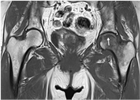

1. 成人の場合、変形性股関節症の頻度が高く、単純X線像で診断可能である。大腿骨頭壊死や軟骨下脆弱性骨折を疑う場合には、MRIを行う(推奨度2)